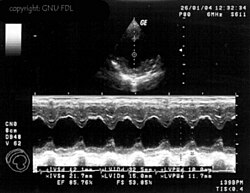

Eine weitere häufig eingesetzte Darstellungsform ist der M- oder TM-Mode (englisch für (time) motion). Dabei wird ein Strahl bei einer hohen Impulswiederholungsfrequenz (1 – 5 kHz) eingesetzt. Die Amplitude des Signals wird auf der vertikalen Achse dargestellt; die von den hintereinander liegenden Impulsen erzeugten Echozüge sind auf der horizontalen Achse gegeneinander verschoben. Diese Achse stellt also die Zeitachse dar.

Bewegungen des Gewebes bzw. der untersuchten Strukturen haben Unterschiede in den einzelnen Impulsechos zur Folge, es lassen sich Bewegungsabläufe von Organen eindimensional darstellen. Die M-Mode-Darstellung ist häufig mit dem B- bzw. 2D-Mode gekoppelt.

Ihre Hauptanwendung findet diese Untersuchungsmethode in der Echokardiografie, um Bewegungen einzelner Herzmuskelbereiche und der Herzklappen genauer untersuchen zu können. Die zeitliche Auflösung dieses Modus ist bestimmt durch die maximale Wiederholrate der Schallimpulse und beträgt schon bei 20 cm Tiefe über 3 kHz.